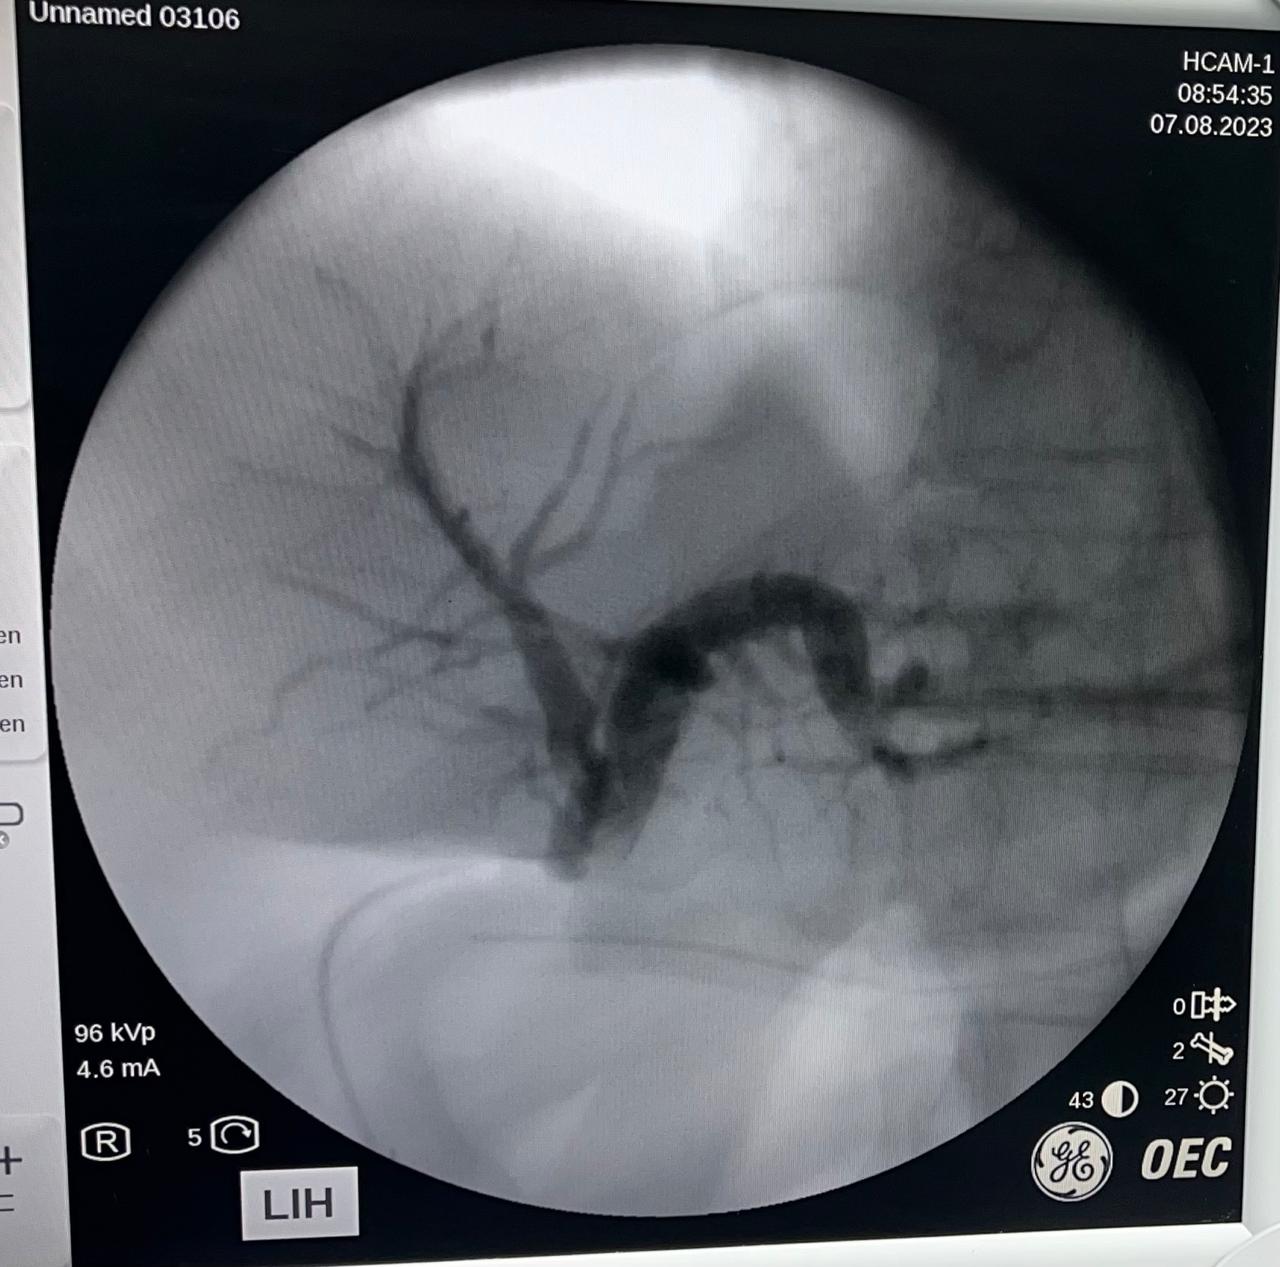

Galería

Cirugías realizadas con éxito